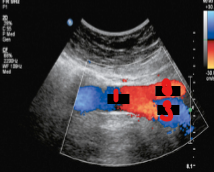

Label the crossed-out structures on this image.

Hepatic artery

Venous confluence

IVC

Left renal vein

Aorta

Celiac artery

Splenic artery